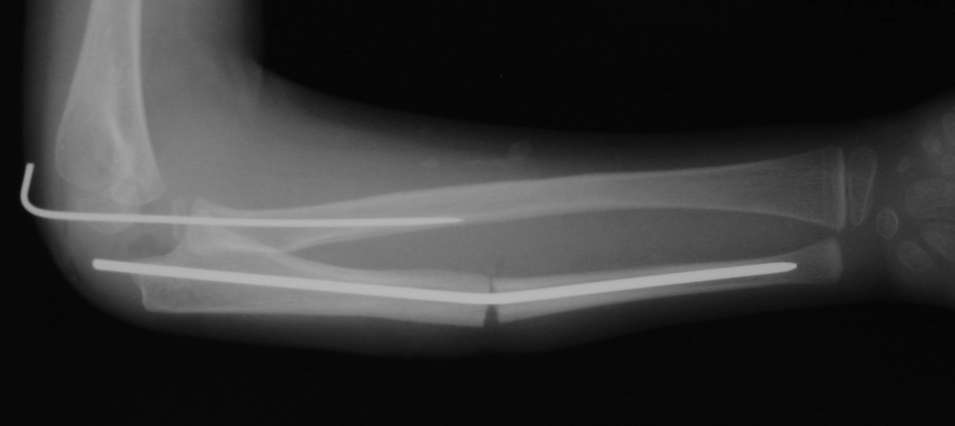

Иллюстрация к лечению застарелого повреждения Монтеджиа

Пациентка клиники детской травматологии ЦИТО